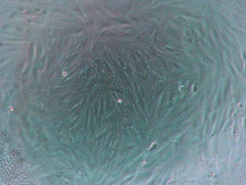

Для наглядности Доктор Фарсалинос продемонстрировал, как выглядят клетки под электронным микроскопом в разных средах: под воздействием чистого воздуха, пара от электронных сигарет и табачного сигаретного дыма.

- Клетки под воздействием чистого воздуха

- Клетки под воздействием пара от электронных сигарет